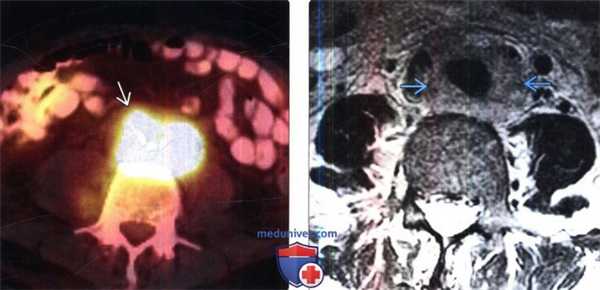

(Слева) ПЭТ/КТ, аксиальная проекция, этот же пациент: ФДГ-положительная лимфаденопатия при НХЛ.

(Справа) МРТ, Т2-ВИ, SS FSE, аксиальная проекция: у этого же пациента выявлено парааортальное образование , имеющее ИС от высокой до умеренной.